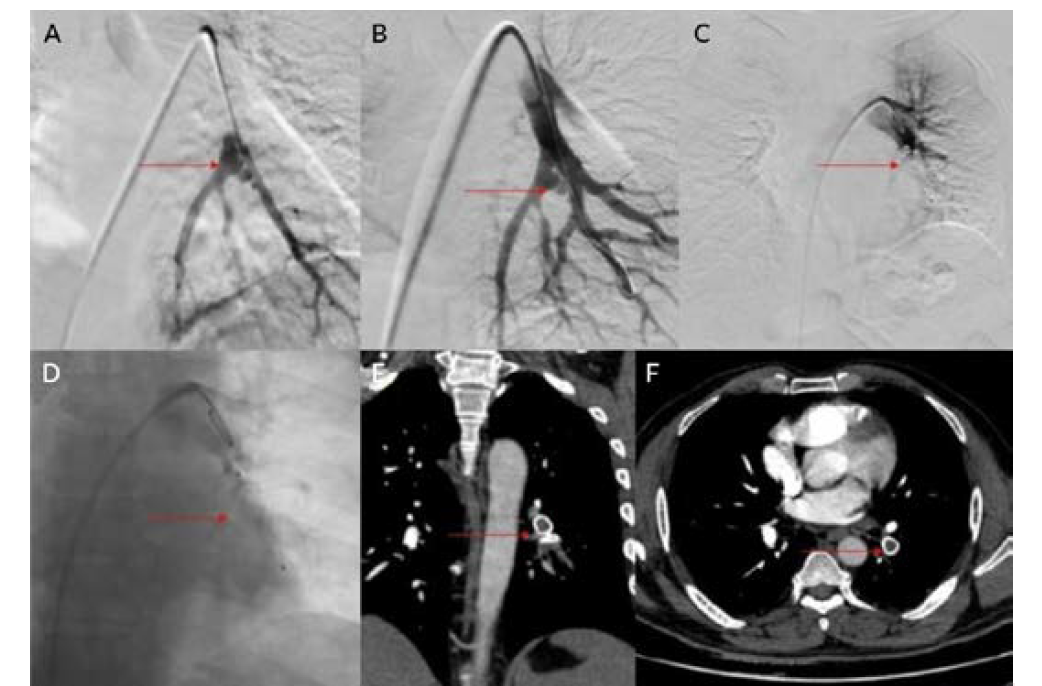

Eight patients were included during this study period; all were men between ages 34 and 61 (Table 1). Positivity to COVID-19 RTPCR test was detected over a period of 2 to 6 months prior to the acute hemorrhage. Six patients presented with massive hemoptysis; 2 presented with severe epistaxis. A contrast-enhanced computed tomography angiography was done in all patients. All 6 patients who presented with massive hemoptysis were detected to have pulmonary arterial pseudoaneurysms with associated cavitary lesions in the lungs (Figure 2). Among the 2 patients who presented with nasal bleed, 1 had a biopsy and culture-proven invasive fungal sinusitis with an internal maxillary artery pseudoaneurysm, probably of mycotic etiology. The second patient also diagnosed with invasive fungal sinusitis had multiple sinonasal debridements outside before presenting with massive epistaxis wherein a diagnosis of internal carotid artery pseudoaneurysm was made, probably secondary to iatrogenic or mycotic etiology. The presence of concomitant COVID-19 infection in these patients predisposed them to impairment of cell-mediated immunity, immune dysregulation, and a decrease in CD4 and CD8 counts, increasing their vulnerability to fungal infections. In 6 patients it was possible to obtain samples for fungal elements through biopsy. Endovascular embolization was performed under local anesthesia in 7 patients, and under general anesthesia in 1 patient. Different embolic agents were used: coils (Figures 3A and 3B), Amplatzer vascular plug (Abbott) (Figures 4A and 4B, Figures 5A and 5B), and glue (Figures 6A and 6B). However, 2 patients underwent lobectomy for extensive parenchymal disease apart from pseudoaneurysm. One patient with pulmonary artery pseudoaneurysm had contrast extravasation into the cavity during the procedure. All patients had cessation of hemorrhage. However, 2 patients required pulmonary lobectomy because of extensive parenchymal disease after embolization for the pseudoaneurysm.

Pulmonary artery pseudoaneurysm is a rare but important entity because of its high risk of life-threatening hemorrhage.2,5,9,10 Peripheral branches of the lower lobe pulmonary artery are most commonly affected.2,5,10 A pseudoaneurysm is different from a true aneurysm because there is no wall except for the hematoma that is surrounding and containing it.6,9,11,12 The etiology of a pulmonary artery pseudoaneurysm is inflammatory erosion secondary to tuberculosis (Rasmussen aneurysm), necrotizing pneumonia, bacterial endocarditis, mucormycosis, or vasculitides (Marfan syndrome, Behçet’s disease, etc.). Other causes include necrotic cavitary lung carcinoma, congenital heart disease, and traumatic injury. Iatrogenic pseudoaneurysm secondary to pulmonary artery catheter placement has also been reported.4-6,9-11 Internal maxillary artery pseudoaneurysm is rare and is more commonly encountered following trauma and iatrogenic injury (Figures 8A and 8B).7,8,13 These patients present with massive or moderate bleeds, which can lead to death in about 50% of cases if left untreated.2,4 The most common artery leading to hemoptysis is the bronchial artery, which constitutes around 80% to 90%.4,5,13 Hemoptysis related to the pulmonary artery constitutes around 10%.10,14 Multidetector computed tomography (MDCT) pulmonary angiography is the modality of choice to diagnose pulmonary artery aneurysms.2,9,10,12 It provides detailed information about the presence, number, size, shape, and origin of pulmonary artery aneurysms.2,9,10 MDCT also allows detailed assessment of the orientation and size of the aneurysmal sac and size of the neck on multiplanar reconstruction.2,10 It also gives an overall idea about the pathology, and the involved lung segment eventually helps in planning the treatment accordingly.4,10,12,14 Digital subtraction angiography has the advantage of allowing endovascular intervention at the time of diagnosis.4,12,14 Ultrasound and magnetic resonance imaging are also used in cases of aneurysms involving neck vasculature.2,14,12

Endovascular intervention is a minimally invasive technique that is used to treat these types of pseudoaneurysms.4-6,11 Pulmonary artery pseudoaneurysms can be treated with multiple techniques, such as coil embolization of the involved artery, plug placement within the involved artery, glue embolization of the aneurysm, and placement of a stent graft across the aneurysm.4,10,11 If the aneurysm is peripherally placed and is not accessible via a transarterial approach, ultrasound-guided injections such as thrombin or glue can be tried.14 The endovascular approach is minimally invasive compared with surgery.9,10 Mortality, morbidity, and complication rates following endovascular intervention are lower compared with surgery.5,11 Hospital stays following endovascular intervention are usually lower.9,10 Endovascular embolization has an initial success rate of 95%, and surgery is reserved for those patients where multiple sittings of embolization have failed.4,5,10